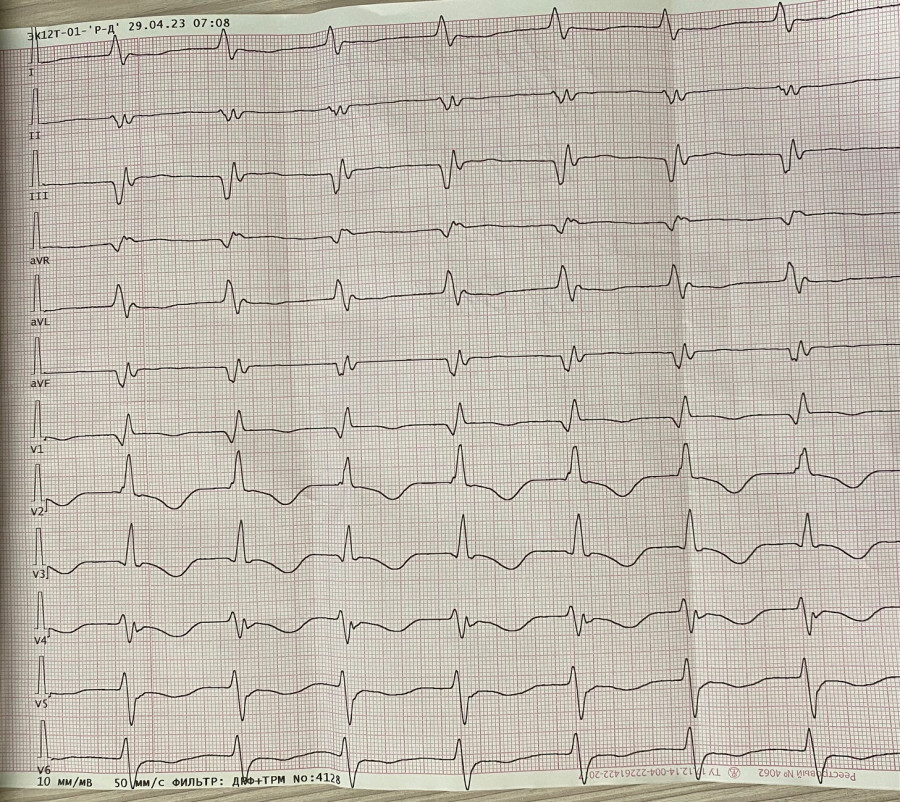

Ускоренный узловой

Обсуждалось здесь https://vk.com/club84409679?w=wall-84409679_13555%2Fall

IMG_4261.jpg

IMG_4261.jpg [ 1.12 MiB | Просмотров: 14296 ]